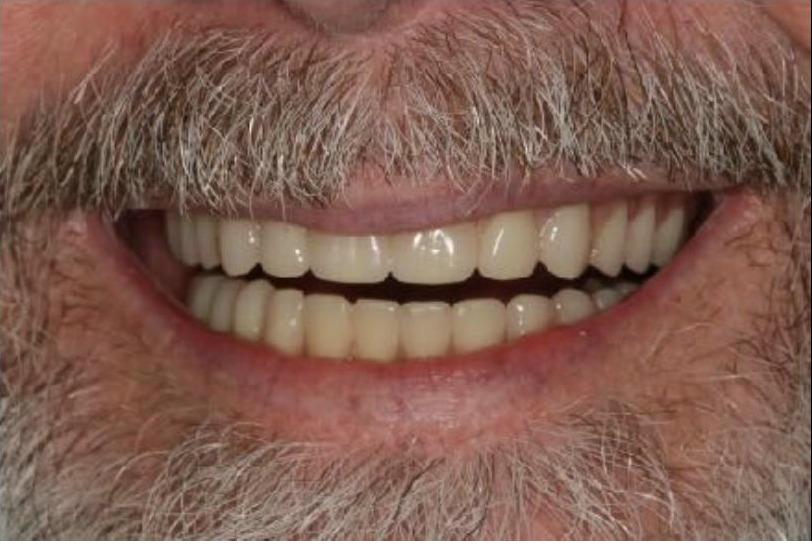

To improve this patient's dental health, esthetics and function, upper and lower implants were placed. I then fabricated an upper screw-retained implant bridge and a lower Overdenture, giving this patient back his smile and function. The patient was thrilled with the result and exclaimed "It looks good! I'll have all the women chasing me! I'd marry me if I wasn't already married!"

To improve this patient's dental health, esthetics and function, upper and lower implants were placed. I then fabricated an upper screw-retained implant bridge and a lower Overdenture, giving this patient back his smile and function. The patient was thrilled with the result and exclaimed "It looks good! I'll have all the women chasing me! I'd marry me if I wasn't already married!"